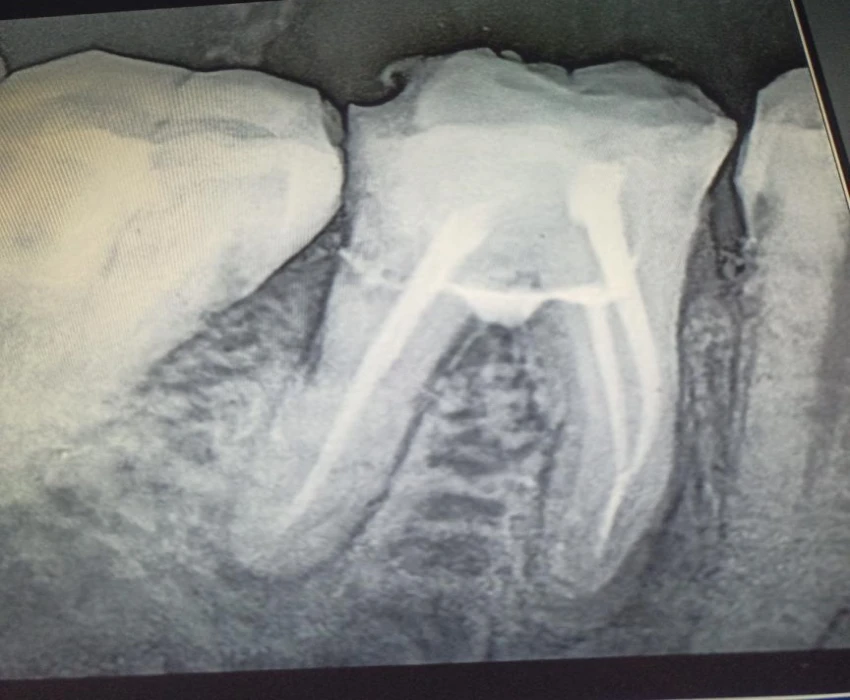

Perforation was detected clinically and radiographically after the removal of caries from the grossly carious tooth.

Canals were located and the working lengths were determined. Canals prepared with crown down technique and obturated using Gutta percha points using lateral condensation technique .

The perforation is sealed with mineral trioxide aggregate-sterile saline paste mixed according to the manufacturer's direction.A cotton pellet was then placed in the pulp chamber to produce a humid ambient for the MTA with the aim of achieving its solidification, and the tooth was temporary filled with Cavit temporary restoration material.